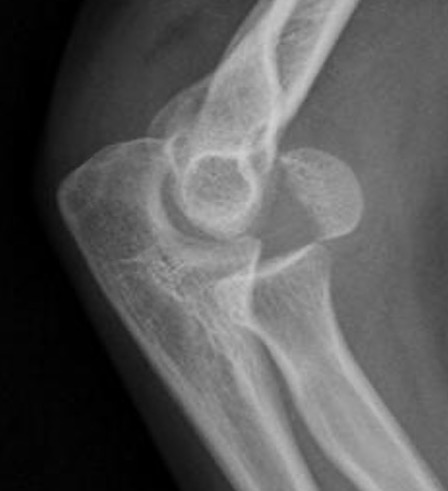

Knee

Approaches